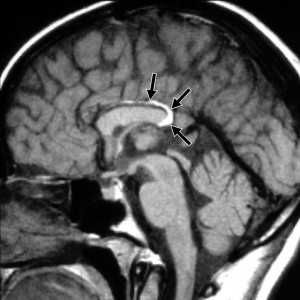

(а) Бесконтрасгная КТ, сагиттальный срез: у молодой женщины, обследуемой по поводу изолированной головной боли, определяется гиподенсная линейная структура, располагающаяся по средней линии.

(б) MPT, Т1 -ВИ, сагиттальный срез: у этой же пациентки выявляется, что линейная структура кри -волинейная межполушарная липома, которая закручивается вокруг заднего отдела гипогенезированного мозолистого тела и направляется в заднюю часть промежуточного паруса. Колено и валик мозолистого тела не полностью сформированы.